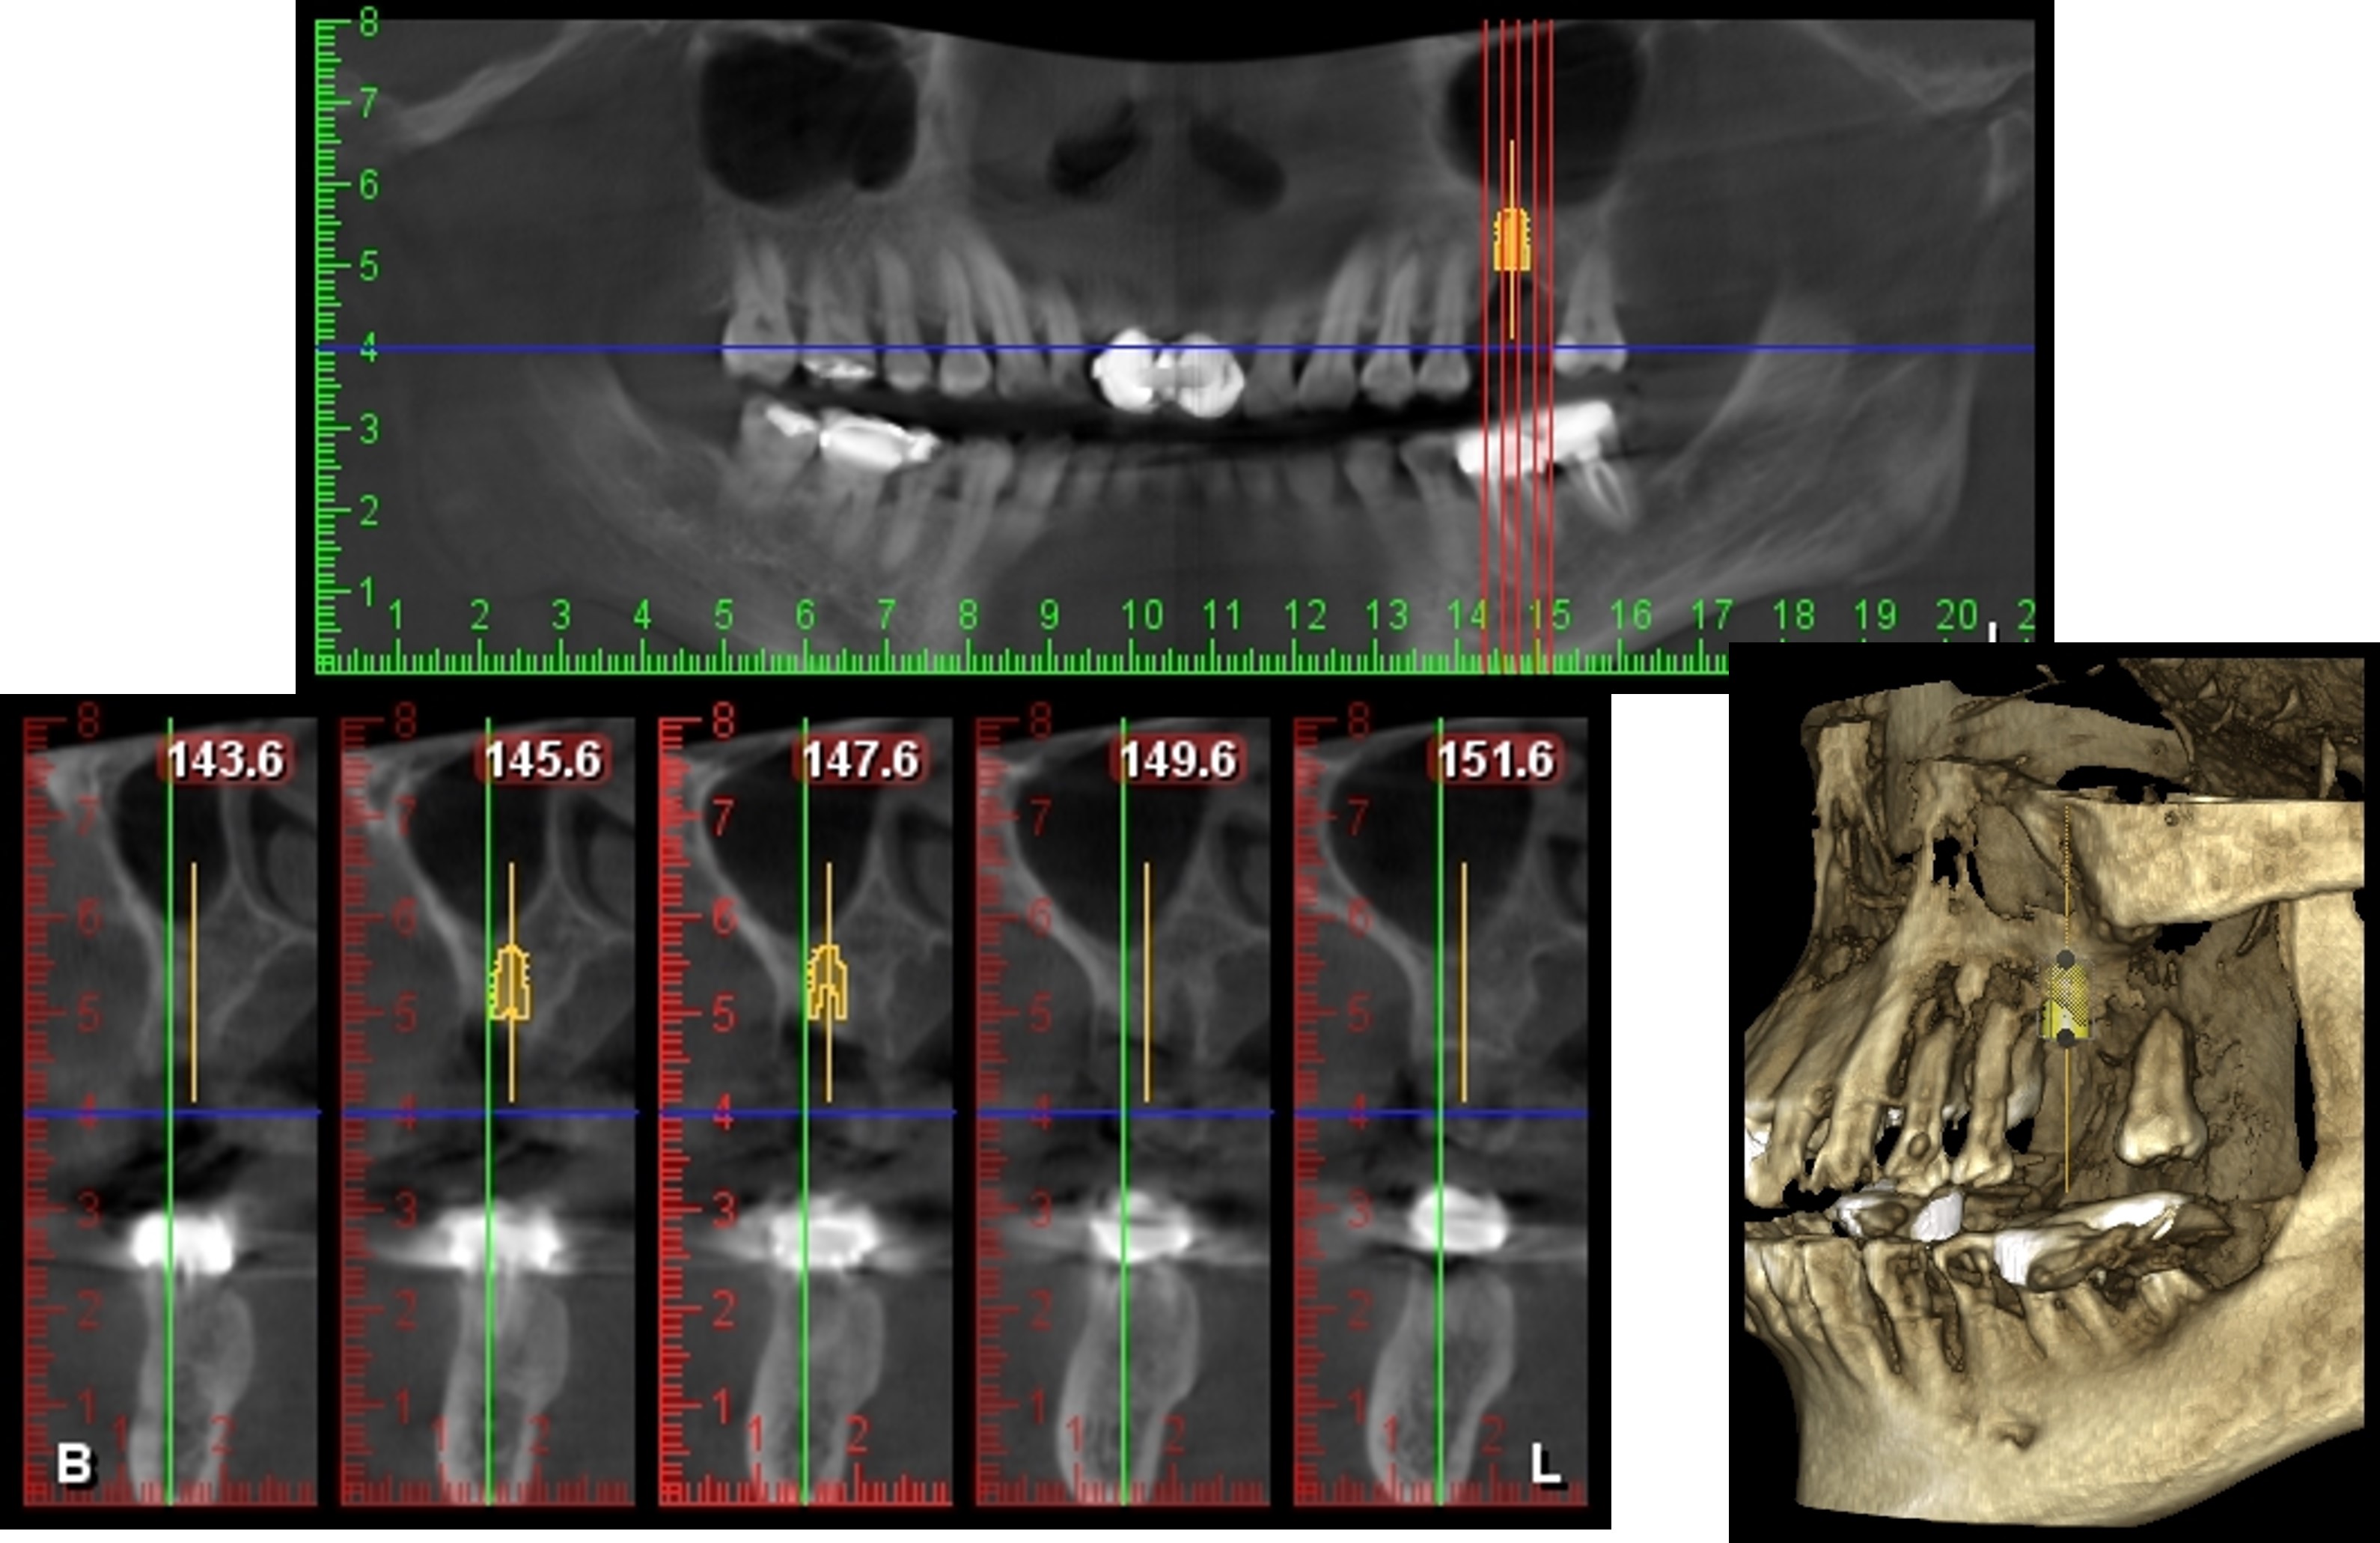

拔牙後再次植牙規畫模擬

植牙、補骨及補骨

植牙後,角度良好

6個月後植牙骨整合